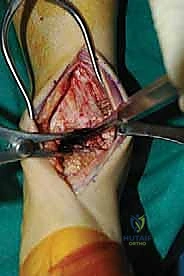

1. الوضعية والشق الجراحي (Positioning and Incision)

يستلقي المريض على ظهره (Supine position). يتم استخدام عاصبة (Tourniquet) حول الفخذ لتقليل النزيف وتوفير رؤية واضحة. يقوم الدكتور هطيف بإجراء شق طولي أمامي فوق مفصل الكاحل، عادة بين وتر العضلة الظنبوبية الأمامية (Tibialis Anterior) ووتر العضلة الباسطة الطويلة لإصبع القدم